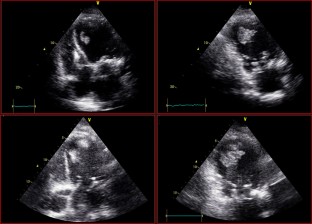

Fig. 4